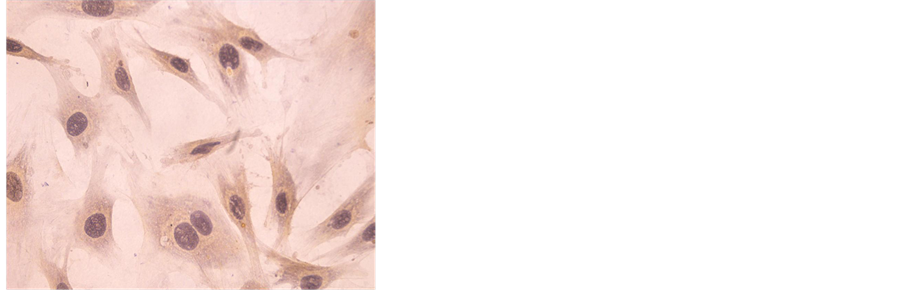

3.1. Identification of Osteoblast-Like Cells

The morphological and biochemical parameters of the cultured cells were

characterised in a preliminary study. A monolayer of spindly to spherical cells with round or elongated nuclei were formed (Figure 1(a)). ALP activity was appeared in 95% of analysed cells after 48 h in culture, verifying the purity of the cultures (Figure 1(b)). Alizarin red stained after 15 days in culture, appeared red calcified nodules (Figure 1(c)).

Figure 1. (a) Osteoblasts cultured at 3d (×200). (b) ALP stained (×40). (c) Alizarin red stained (×200). (d) TRAP stained (×100). (e) Scanning electron microscopic picture of lacunae (×1400).